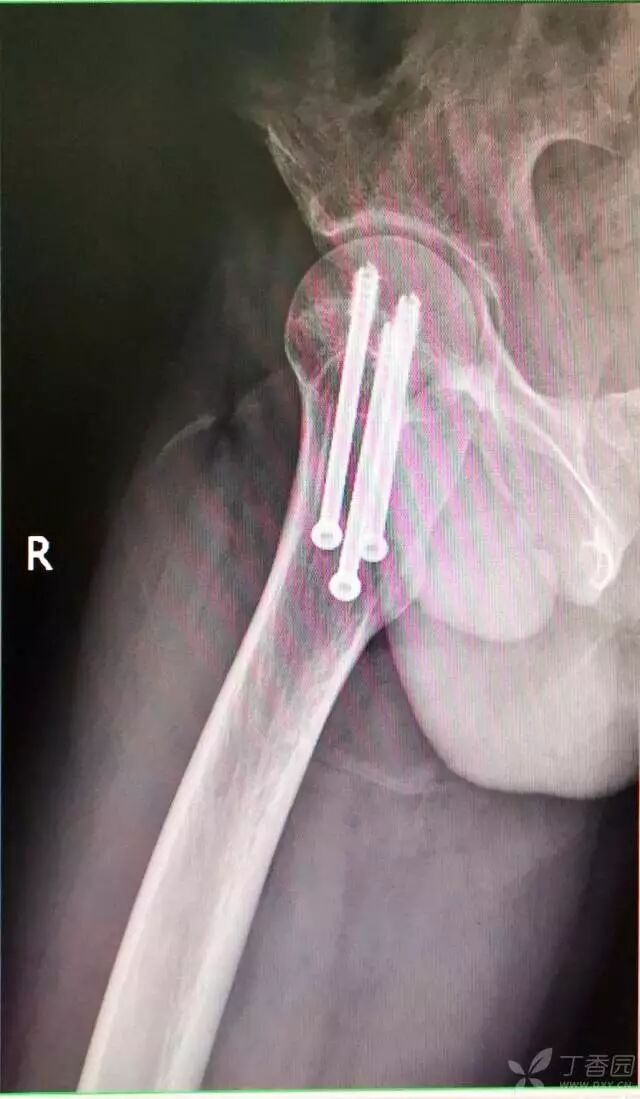

8. 最后测深依次拧入合适长度的螺钉

牵引床怎么用视频详解:如何不使用牵引床做好一台股骨颈骨折?_https://www.jmylbn.com_新闻资讯_第17张